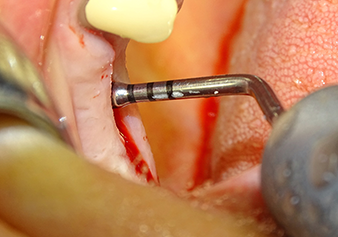

The implant bed is widened to 3.0 mm with the I3A instrument

Fig.5: In the next step, the implant bed is widened to 3.0 mm with the I3A instrument (power 100%, coolant 80%). The depth marks reliably prevent the preparation from going too deep.

The Schneiderian membrane is stretched 1.5-2 mm above the bony access

Fig.4: Intermediate check: The bone height above the maxillary sinus floor is approx. 4 mm palatal and buccal; the Schneiderian membrane is stretched 1.5-2 mm above the bony access.